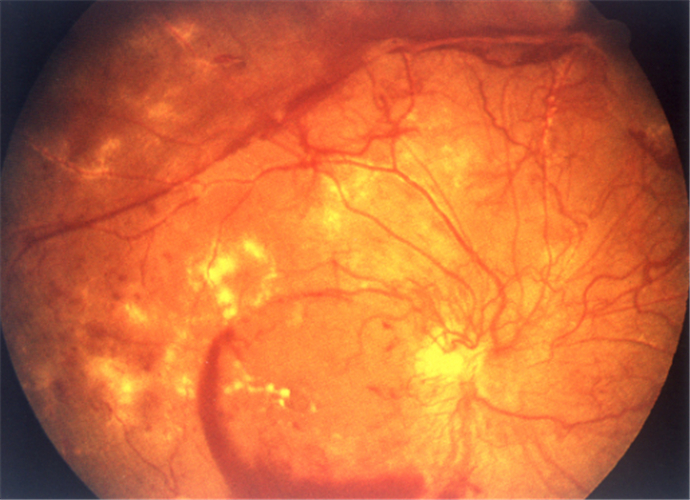

嚴重視網膜脫落

嚴重的視網膜脫落